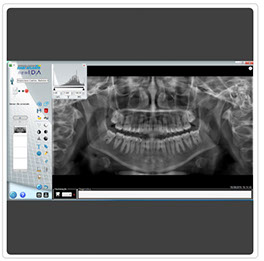

Solución de Rayos-X Intraorales New IDA

La imagen de la evolución

New IDA es el sensor digital intraoral de la linea Eagle Image con soluciones eficientes de las imágenes para un diagnóstico más nítido, preciso y seguro.

Los cuidados de la salud bucal han alcanzado un modo más avanzado.

Optimice su tiempo, tómese sus radiografías con New Ida en OEP.